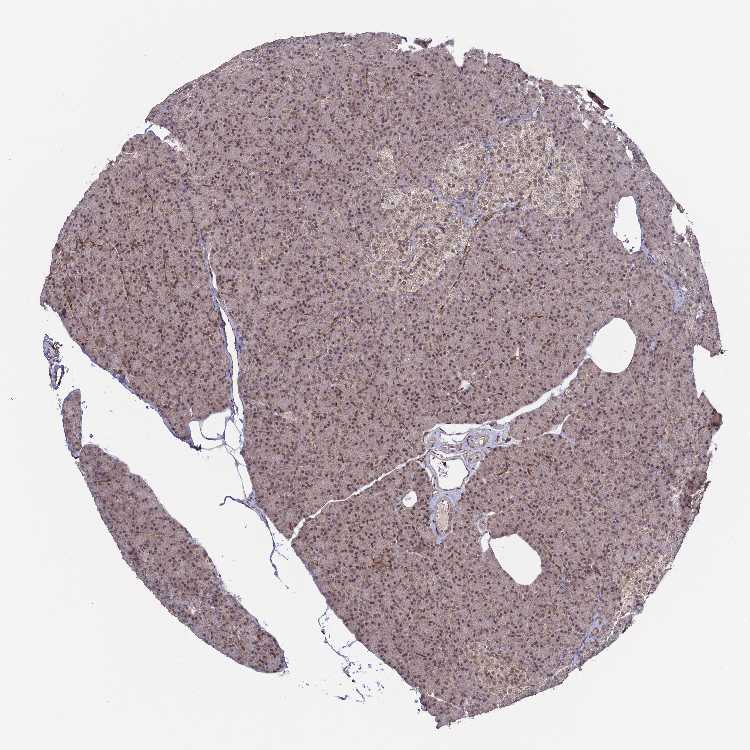

PANCREAS - Antibody stainingi

Antibody staining in the annotated cell types in the current human tissue is reported as not detected, low, medium, or high, based on conventional immunohistochemistry profiling in selected tissues. This score is based on the combination of the staining intensity and fraction of stained cells.

Each image is clickable and will lead to virtual microscopy that enables deeper exploration of all samples and also displays staining intensity scores, fraction scores and subcellular localization as well as patient and tissue information for each sample.

Antibody HPA042703

Exocrine glandular cells Medium

Pancreatic endocrine cells Low